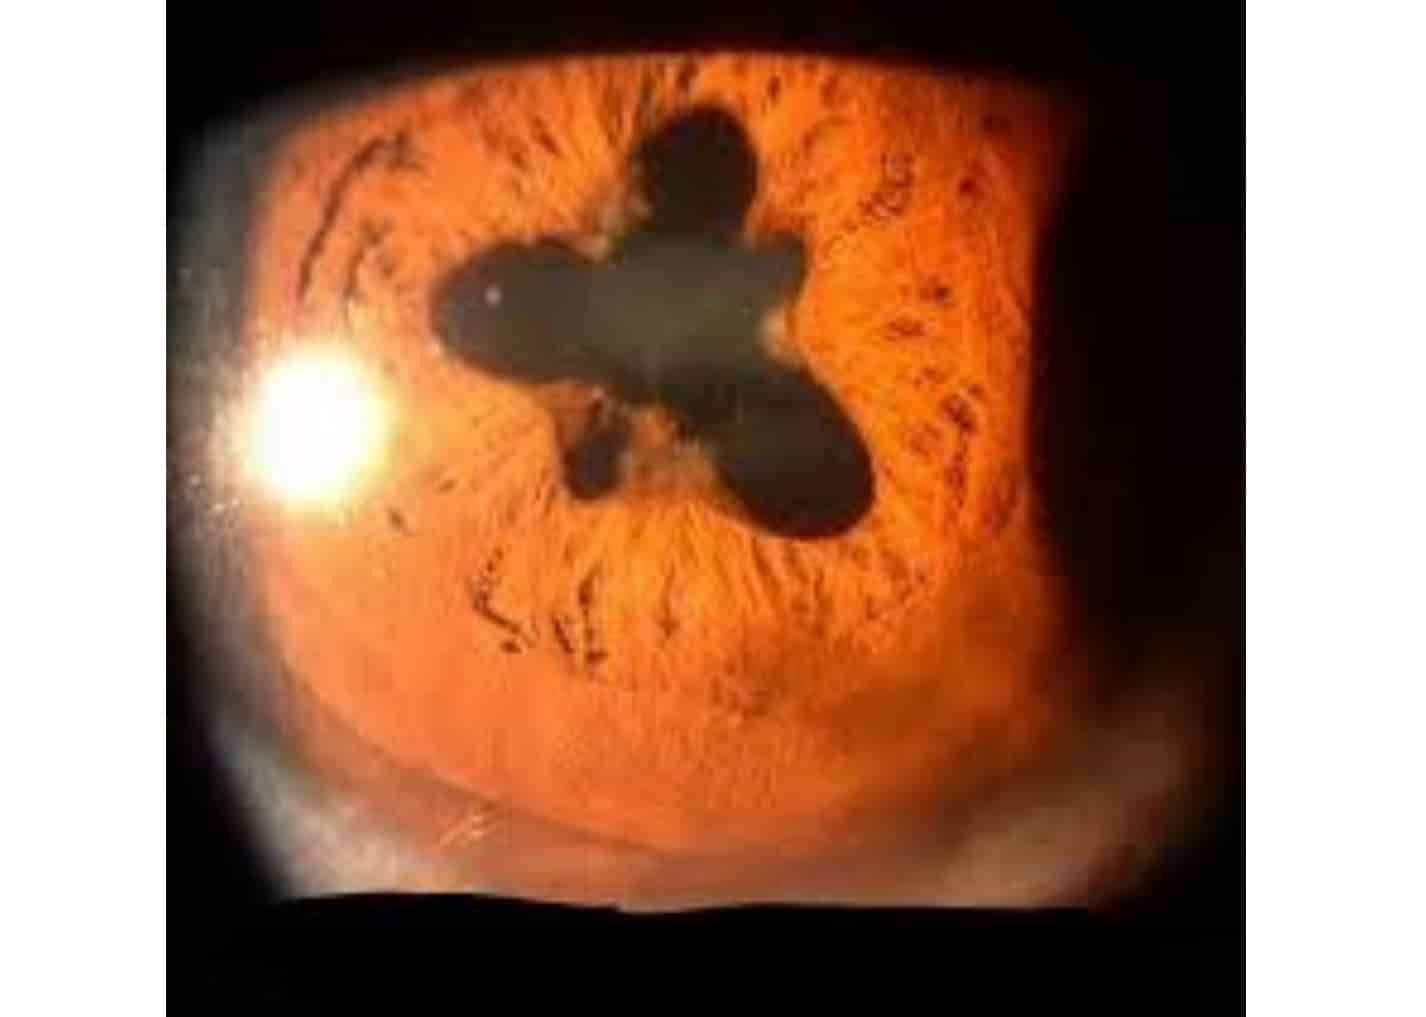

Festooned Pupil Seen In . Web anterior uveitis (iritis) is the inflammation of the anterior chamber and the iris. Web when light reaches a pupil there should be a normal direct and consensual response. Web symptoms of pupil abnormalities. Due to the application of cycloplegic topicals, often some parts of the posterior synechiae dilates thus making the pupil festooned shaped. Web festooned pupils are seen in iritis, where the posterior synechiae distort the pupil shape; Uveitis is often idiopathic, but it. The affected pupil may be more dilated than normal and might be slower to respond. Web adie syndrome is a rare neurological issue that affects the pupil of the eye and the autonomic nervous system. Web the festoon is a condition in which the attenuated orbicularis muscle and lax skin forms a cascading drape of edematous excess skin. Generally asymptomatic, although pupil abnormalities may be. It is more evident after. An rapd is diagnosed by observing paradoxical.

Due to the application of cycloplegic topicals, often some parts of the posterior synechiae dilates thus making the pupil festooned shaped. Web festooned pupils are seen in iritis, where the posterior synechiae distort the pupil shape; An rapd is diagnosed by observing paradoxical. Generally asymptomatic, although pupil abnormalities may be. Web when light reaches a pupil there should be a normal direct and consensual response. Uveitis is often idiopathic, but it. Web symptoms of pupil abnormalities. Web adie syndrome is a rare neurological issue that affects the pupil of the eye and the autonomic nervous system. It is more evident after. Web the festoon is a condition in which the attenuated orbicularis muscle and lax skin forms a cascading drape of edematous excess skin.